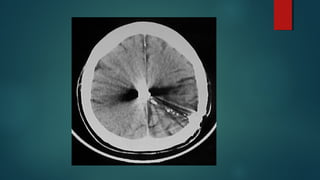

Este documento es el programa para un taller de imágenes del curso de emergencia 2015 impartido por el Dr. Víctor Delgado. El taller se centra en el uso de imágenes médicas para el diagnóstico y tratamiento de pacientes en coma traumático según la base de datos de Marshall. El Dr. Delgado es el único instructor repetido a lo largo del documento.